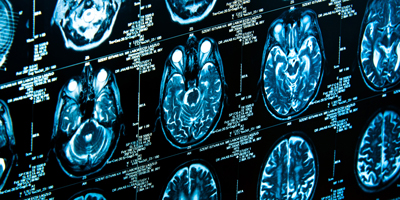

Learn how Alzheimer’s disease affects the brain.